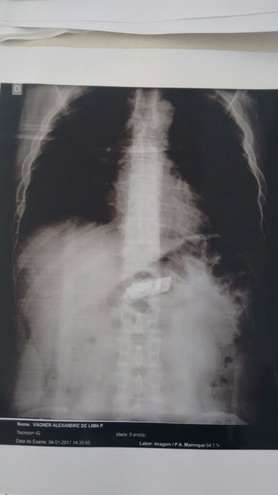

Segundo a SAP, desconfiados do comportamento de três presos, agentes os levaram até o Hospital Regional para exames e no raio-x, apareceu o aparelho no estômago de um deles

Segundo a SAP, desconfiados do comportamento de três presos, agentes os levaram até o Hospital Regional para exames. No raio-x, apareceu um invólucro no estômago de V. A. L. P. , que confessou estar levando o aparelho no próprio corpo.